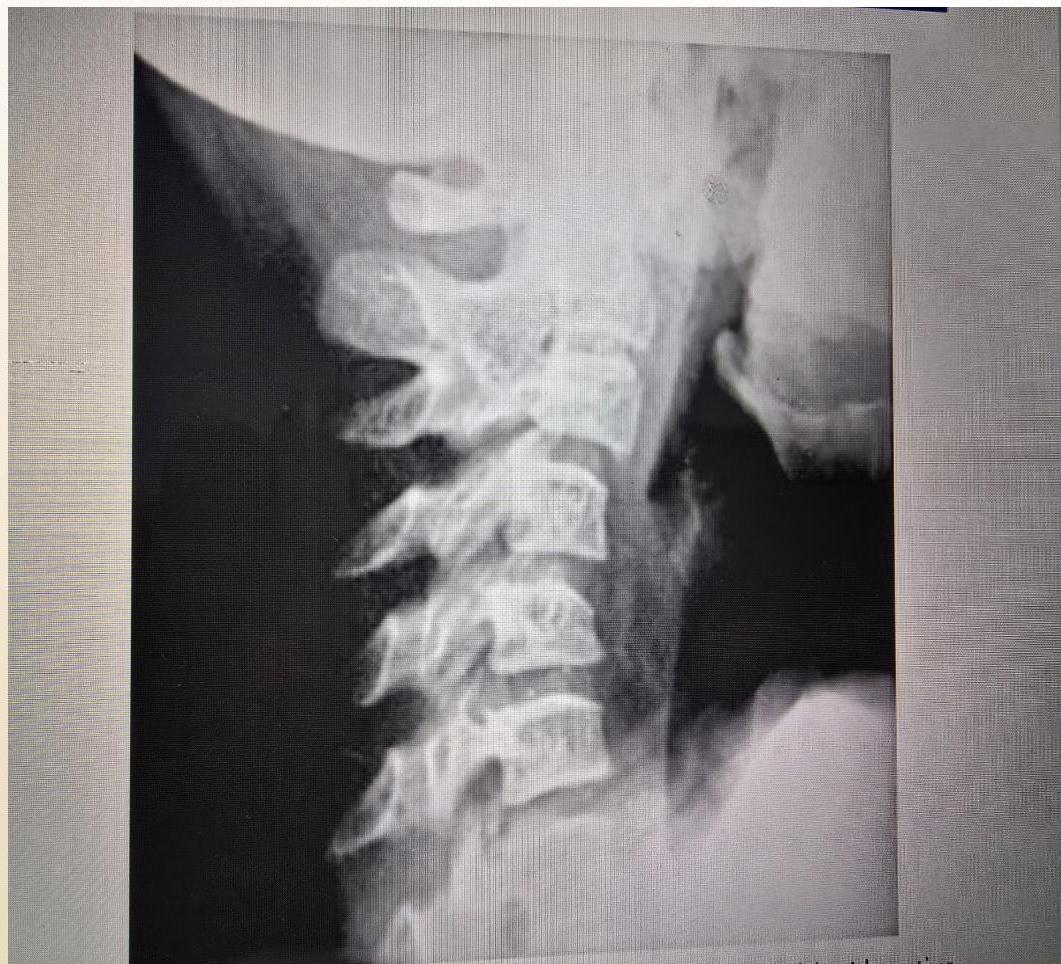

- Cervical Spine:

- Decreased extension is asymptomatic.

- Can lead to subluxation (typically C2 on C3).

- Radiographic: Fusion of neural arch (C2-C3), narrowing/erosion of remaining joints, obliteration of apophyseal space, loss of normal lordosis.

Cervical Spine:

(Left: Fusion of neural arch C2-C3. Right: Flexion/extension views)